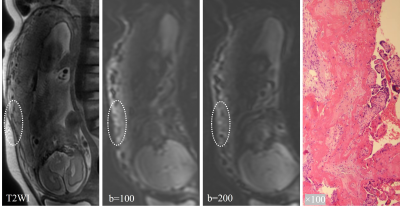

Figure 4 showed the characteristics of IVIM images of the placenta in patients with PA. Part of the basal plate disappeared (>10mm), and the myometrium could not be separated from placenta. T2WI images displayed partial bulge of placenta with PI, and IVIM images showed interrupted low signal bands of the basal layer at the same location (Figure 5). T2-dark bands, discontinuous myometrium, abnormal intraplacental vascularity and placental bulge are some of the most common signs of PAS diagnosed by conventional MRI. As shown in Table 2, comparing these signs of conventional MRI, sign of discontinuous basal plate in IVIM achieved the highest diagnostic sensitivity (92.6%) with an AUC of 0.892.

Figure 4. The characteristics of IVIM images of the placenta in patients with PA.Part of the basal plate disappeared (>10mm), and the myometrium could not be separated from placenta.

Figure 4. The characteristics of IVIM images of the placenta in patients with PI. IVIM images showed interrupted low signal bands of the basal layer at the same location.